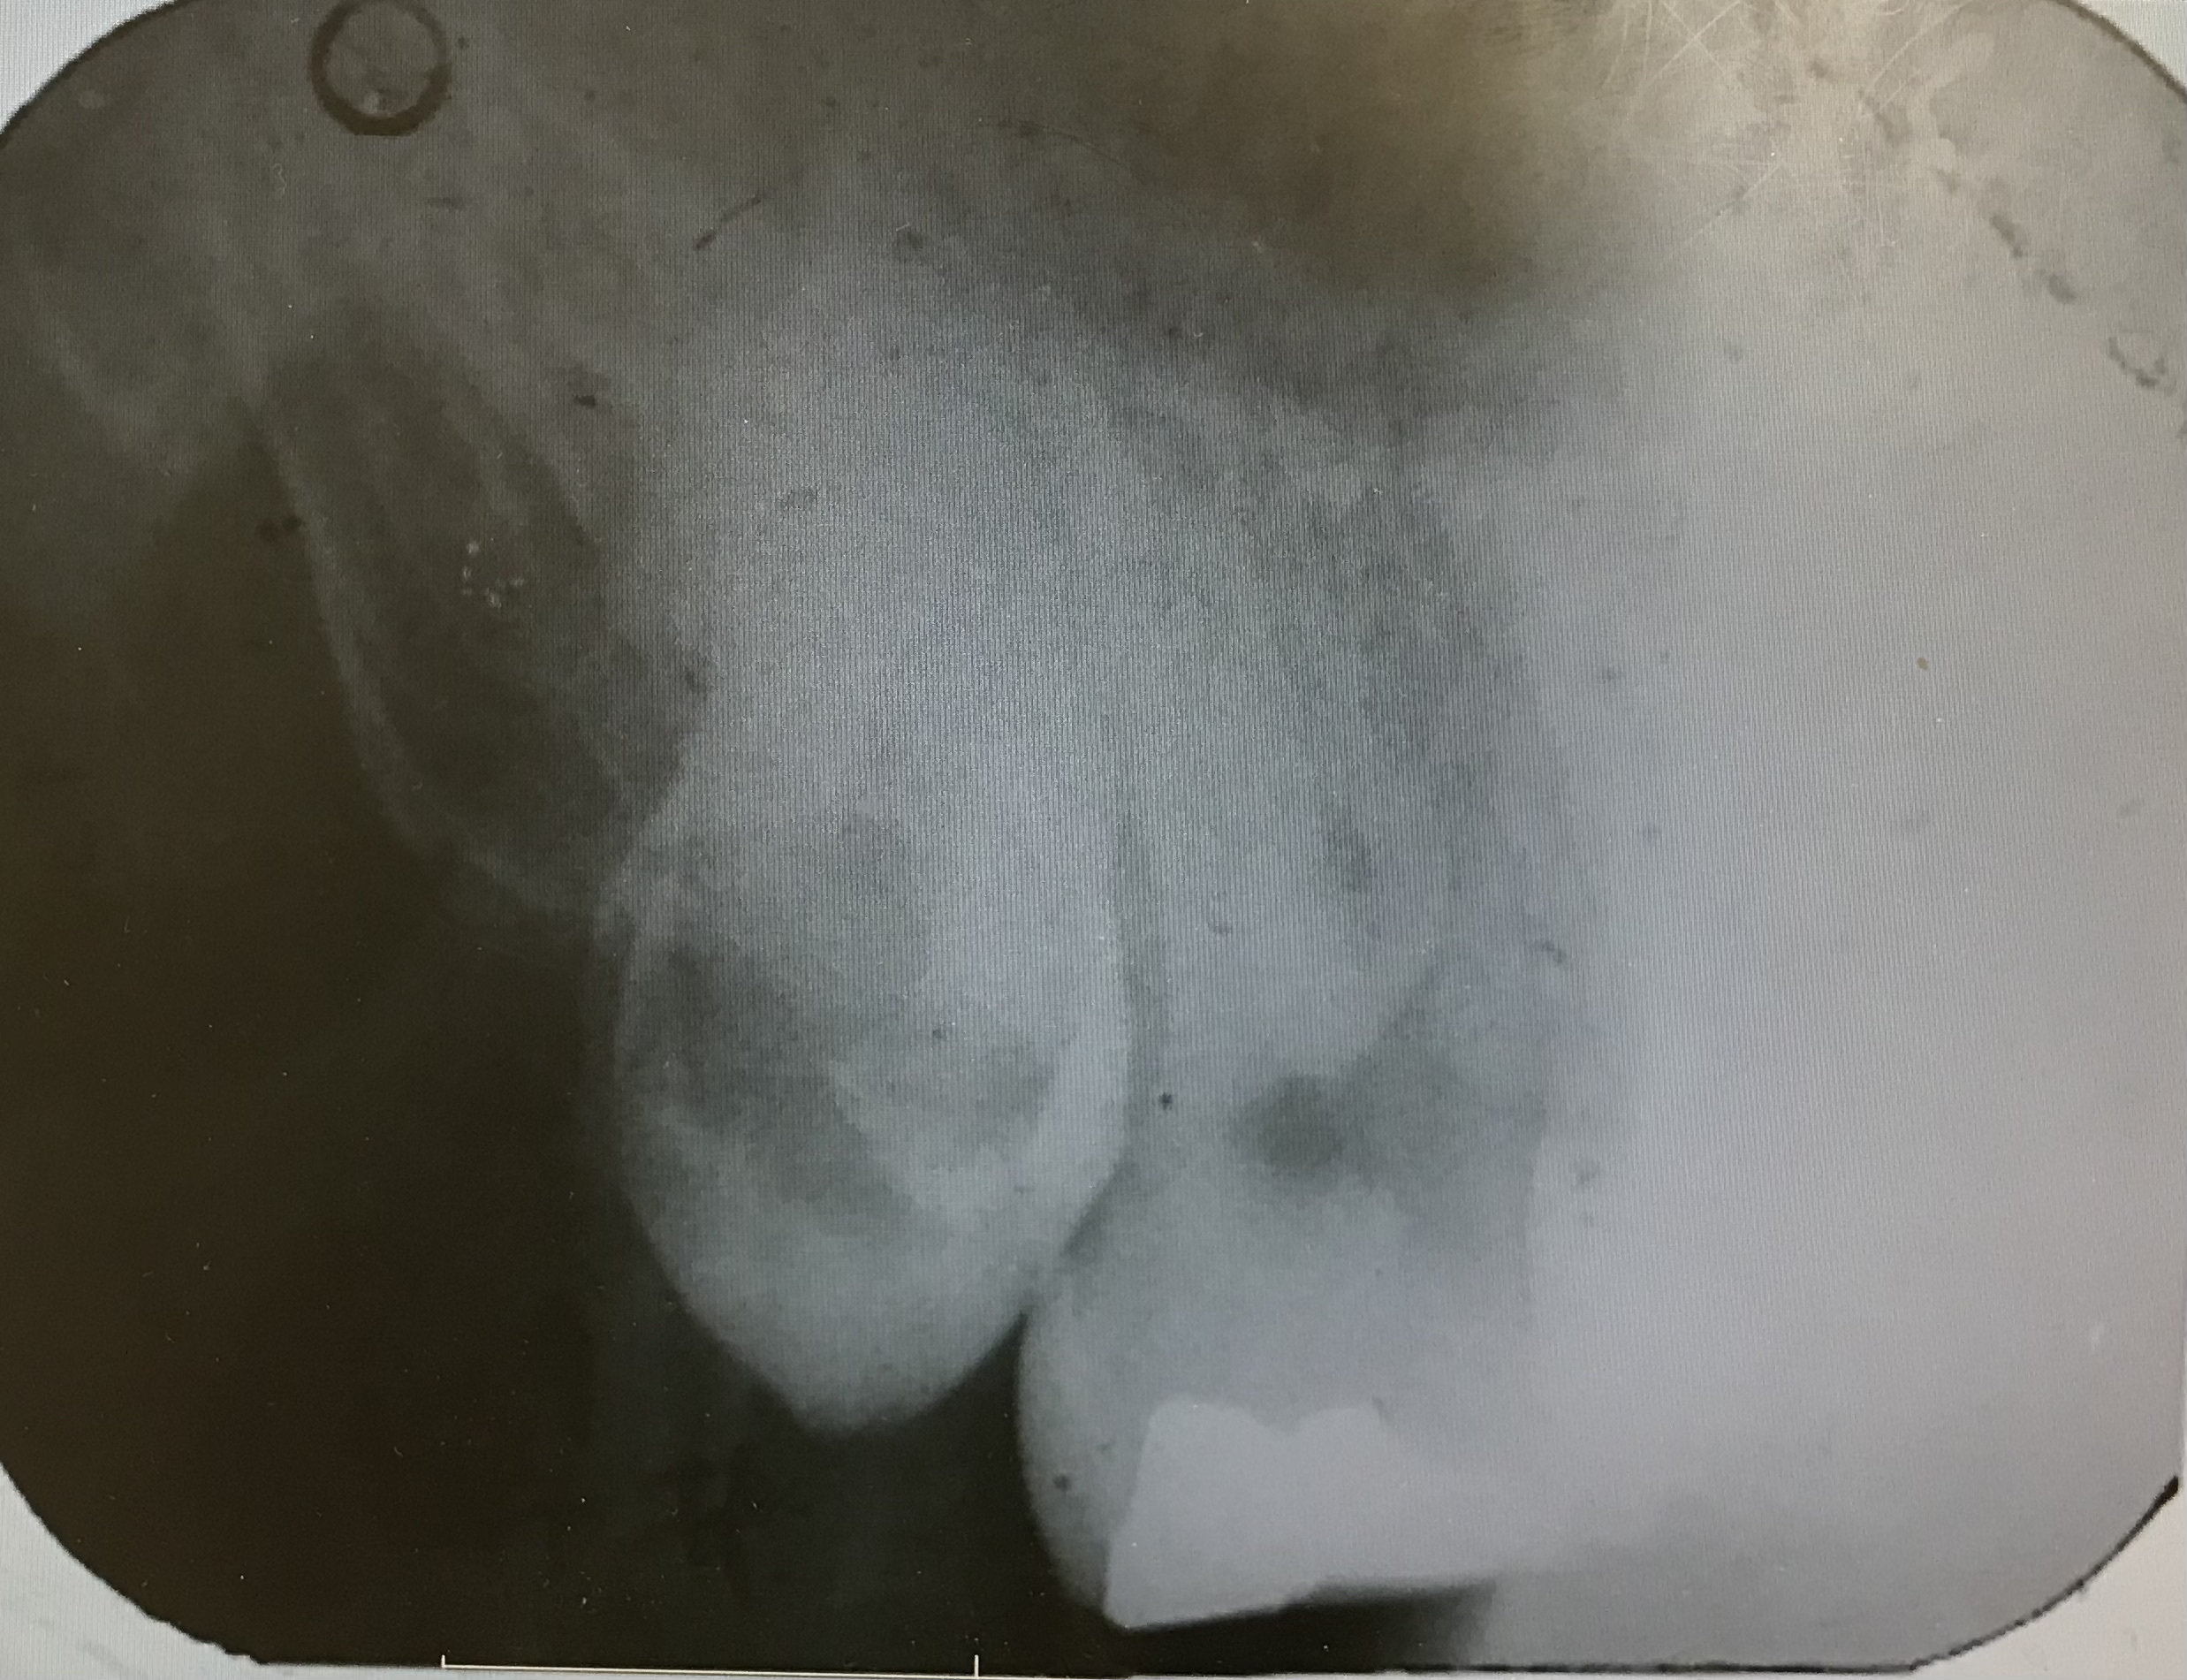

☆☆☆

神経と親知らずが非常に近く,抜歯をすると麻痺が出る可能性が非常に高そうです.二回に分けて親知らずを抜くことにしました.

まず,歯の頭の部分を分割します.神経に非常に近いので分割も細心の注意を払って行います.

歯の頭だけを除去しました.そのスペースに根っこが移動してくるのを半年ほど待ちます.これももちろん保険適応です.自費のところもあるみたいです.